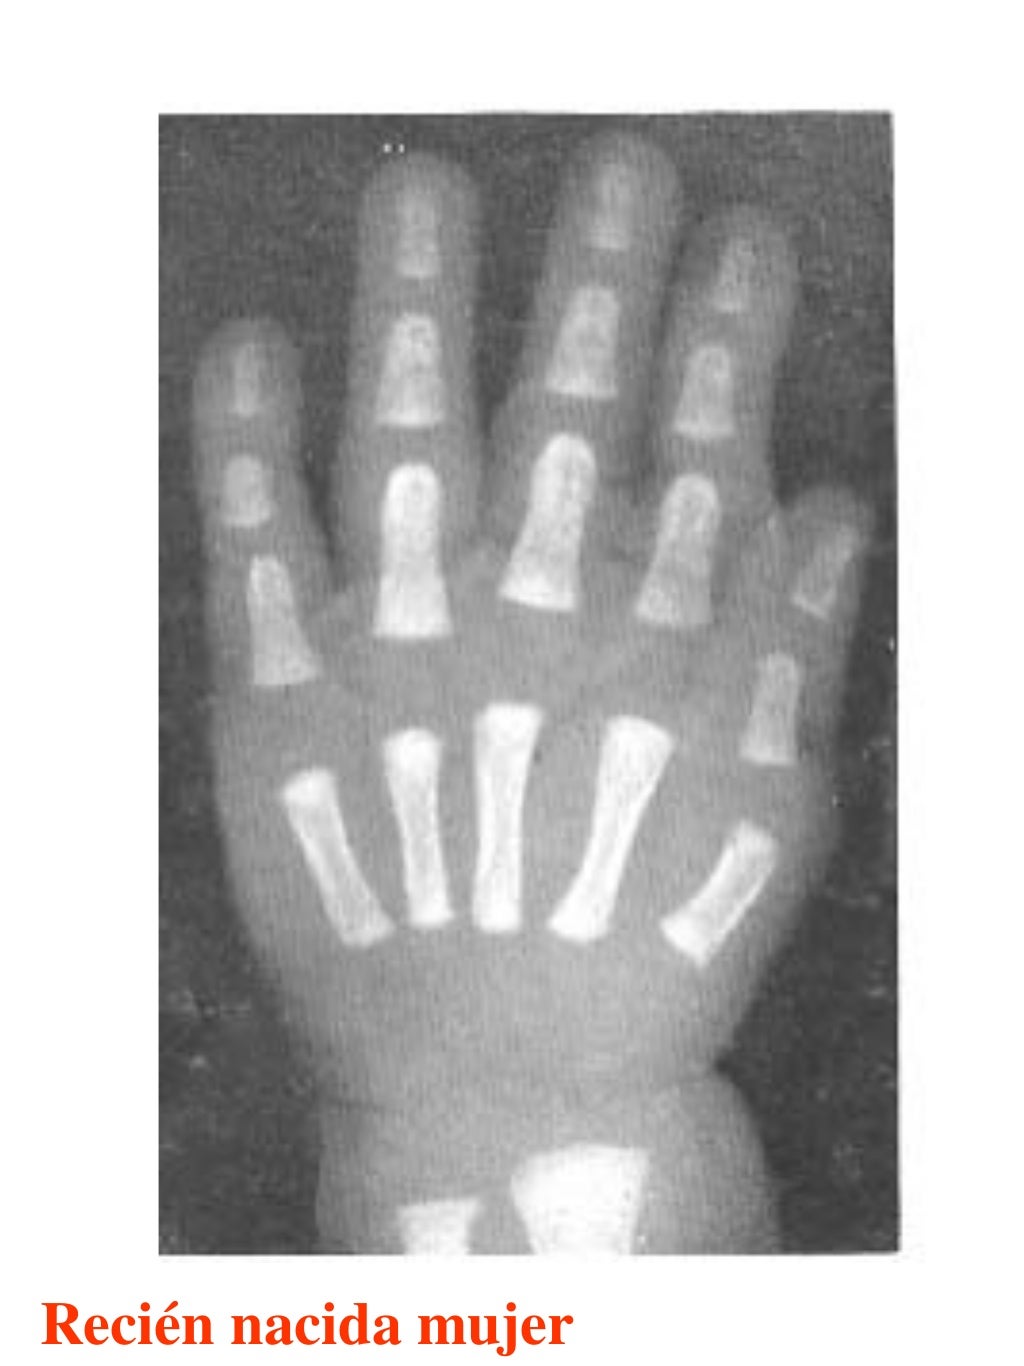

Tablas De Greulich Y Pyle . Scribd is the world's largest social reading and publishing site. This systematic review summarizes the. The radiographic atlas of skeletal development of the hand and wrist by ww greulich and si pyle is a classic radiological. The standards established by greulich and pyle, undoubtedly the most popular method, consist of two series of standard plates. The greulich and pyle method is one of the two main ways to assess the bone age of children. El documento lista las edades. Both main methods of bone age. 153 recomendaciones • 616,869 vistas. Atlas greulich y pyle | pdf | descarga gratuita. The greulich and pyle atlas is used to estimate the age of children and adolescents.

Tablas De Greulich Y Pyle The standards established by greulich and pyle, undoubtedly the most popular method, consist of two series of standard plates. The standards established by greulich and pyle, undoubtedly the most popular method, consist of two series of standard plates. El documento lista las edades. This systematic review summarizes the. The greulich and pyle method is one of the two main ways to assess the bone age of children. Both main methods of bone age. Scribd is the world's largest social reading and publishing site. 153 recomendaciones • 616,869 vistas. Atlas greulich y pyle | pdf | descarga gratuita. The greulich and pyle atlas is used to estimate the age of children and adolescents. The radiographic atlas of skeletal development of the hand and wrist by ww greulich and si pyle is a classic radiological.